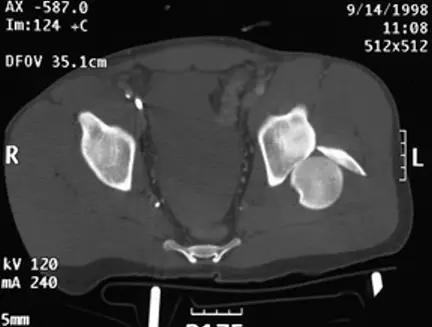

20歲男性病人因車禍左髖關節腫痛。圖為本次就診之左髖關節 X 光攝影及電腦斷層影像。最可能的診斷為何?

本題核心在於鑑別髖關節脫位的方向與合併骨折,特別是後方髖關節骨折脫位(posterior hip fracture-dislocation)的影像學特徵與臨床意義。

進一步於 axial CT 平掃中,可見左股骨頭完全移出髖臼,位於 posterior acetabular rim 之外,且緊鄰一塊骨片,代表 posterior rim fracture。周邊尚見關節腔內軟組織密度,符合急性髖關節骨折脫位的表現(radiopaedia.org)。